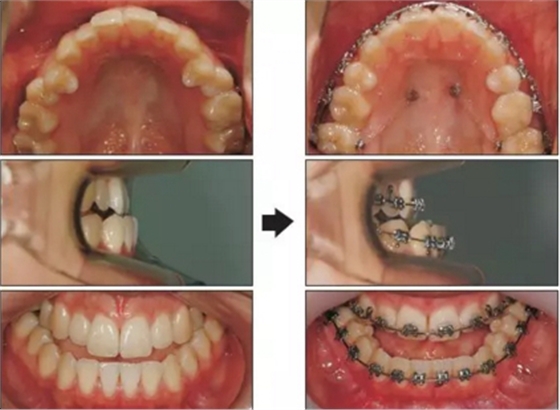

拔除上頜第一前磨牙后,上牙上0.022-槽溝的托槽??紤]到上牙列關(guān)閉間隙需要的時(shí)間,下頜托槽在上牙初始排齊整平后安裝。在10個(gè)月的治療后,在雙側(cè)腭部各植入一枚8mm長(zhǎng)的支抗釘。用從支抗釘?shù)缴项M第二磨牙舌側(cè)扣的橡皮鏈壓低上頜磨牙。為了解決合平面傾斜,較左側(cè)更多地壓低右側(cè)磨牙。14個(gè)月的治療后,完全關(guān)閉了拔牙間隙,且上頜磨牙被壓低(Figure 3)。在術(shù)前正畸后,上下切牙角度達(dá)到正常范圍內(nèi)(upper occlusal plane to upper incisors, 59.1°; lower occlusal plane to lower incisors, 78.2°; upper occlusal plane to FH, 13.1°)。重新評(píng)估后確定可以進(jìn)行單頜手術(shù)獲得美觀面型。在手術(shù)10個(gè)月后移除矯治器??偟闹委煏r(shí)間為24個(gè)月。1周內(nèi)開始應(yīng)用Hawley保持器。